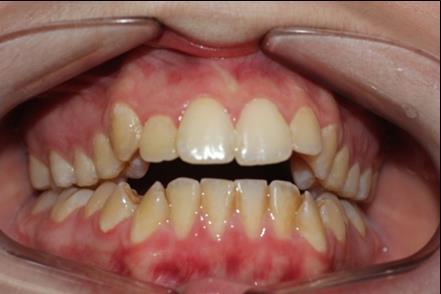

The patient, a 21-year old woman , had a convex profile , class I dental malocclusion ,anterior open bite of 4 mm . She was a mouth breather and presented tongue thrust. Her chief complain was the anterior open bite .(Figure 1)

Figure 1.Pretreatment intraoral photography